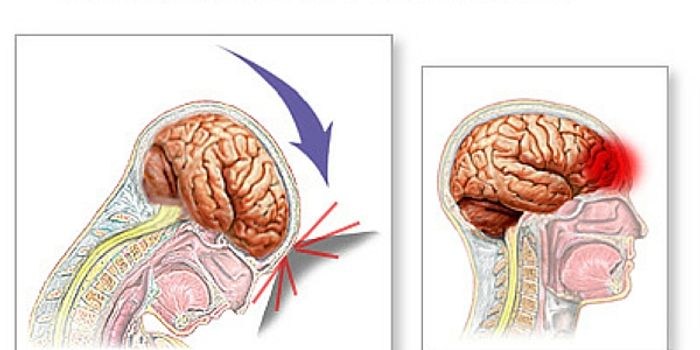

JUN 07, 2016NeuroscienceA traumatic brain injuries, or TBI, can be devastating and have long-lasting effects. In children these injuries can be ...

MAY 12, 2016NeuroscienceTraumatic brain injuries, or TBI, are known to cause a variety of problems. TBI has been indicated in Chronic Traumatic ...

MAR 23, 2016NeuroscienceWhile the subject of brain injuries, concussion and Chronic Traumatic Encephalopathy (CTE) have swirled around the NFL f ...

DEC 20, 2015Health & MedicineChildren commonly get concussions. Usually, those concussions happen while playing a sport. Concussions are caused by a ...